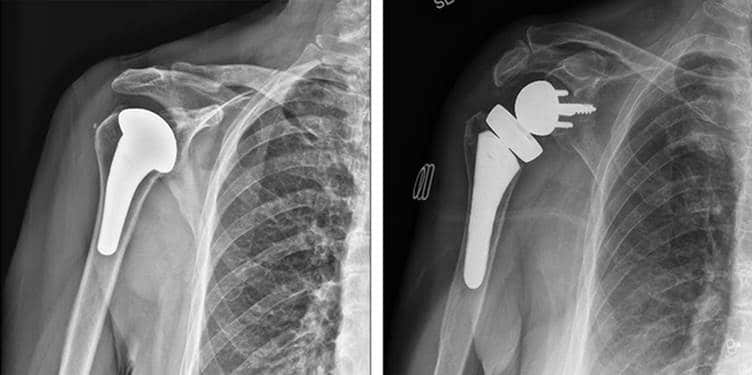

• استبدال مفصل الكتف العكسي:

يُستخدم هذا الإجراء لعلاج التهاب المفاصل الشديد أو تمزقات الكفة المدورة غير القابلة للإصلاح، ويغير آلية عمل الكتف للسماح للعضلات الأخرى بتحريكه.